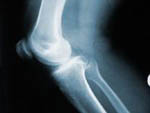

Θεσσαλονίκη: Ένα από τα συχνότερα προβλήματα υγείας στην τρίτη ηλικία είναι η οστεοαρθρίτιδα. Πρόκειται για εκφυλιστική νόσο των αρθρώσεων, που αφορά κυρίως στις αρθρώσεις που δέχονται φορτία (ισχίο, γόνατο και σπονδυλική στήλη) και χαρακτηρίζεται από πόνο και ελάττωση της κινητικότητας της άρθρωσης, με αποτέλεσμα σε προχωρημένα στάδια να επέρχεται η καθήλωση του ασθενούς στο κρεβάτι.